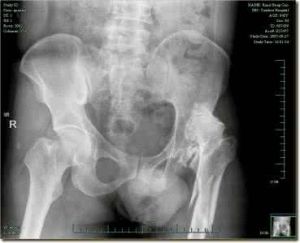

1、先天性髖關節脫位的最早表現是髖的外展外鏇受限制,即讓孩子平躺於床上,先將其膝蓋彎曲至90度,後將髖部緩慢外展,不能平置於床上。此外,如果單冊脫位的還可見到患脫位的下肢比另一冊短。因此,如果孩子學走路前見到這樣的症狀時,就要想到孩子是否患先天性髖關節脫位的可能,應該及時帶孩子到醫院檢查。

2、如果孩子已經開始學步,看到孩子行走時出現“鴨步狀態”,及孩子在走路時身體向兩冊一搖一擺,猶如鴨子在走路;而站立時可以看出孩子腰部向前凸出的特別明顯,就要考慮孩子有可能患先天性髖關節脫位。

3、孩子1歲以上時發現有異常的步態。雖然沒有“鴨行”狀態,但在走路時一蹺一蹺的姿態,除了跛行外,孩子其他表現正常,沒有因疼痛哭鬧的表現,也應及時帶孩子到醫院檢查。

先天性髖關節脫位的治療越早效果越好。儘可能在孩子出生6個月內就給予治療。如果能在新生兒期發現,可以避免手術,用吊帶或手法復位再用支架治療;稍大一些則需要上“蛙形”石膏。一般1歲內的孩子一般需要麻醉,也不需要任何手法整復,只需要用夾板將患兒的髖部固定於某一部位。1-3歲的孩子則往往需要用手法整復或用牽引來整復。如延遲到4歲後進行整復,孩子需要進行手術,將遭受很大的痛苦,效果也不如早期的治療。